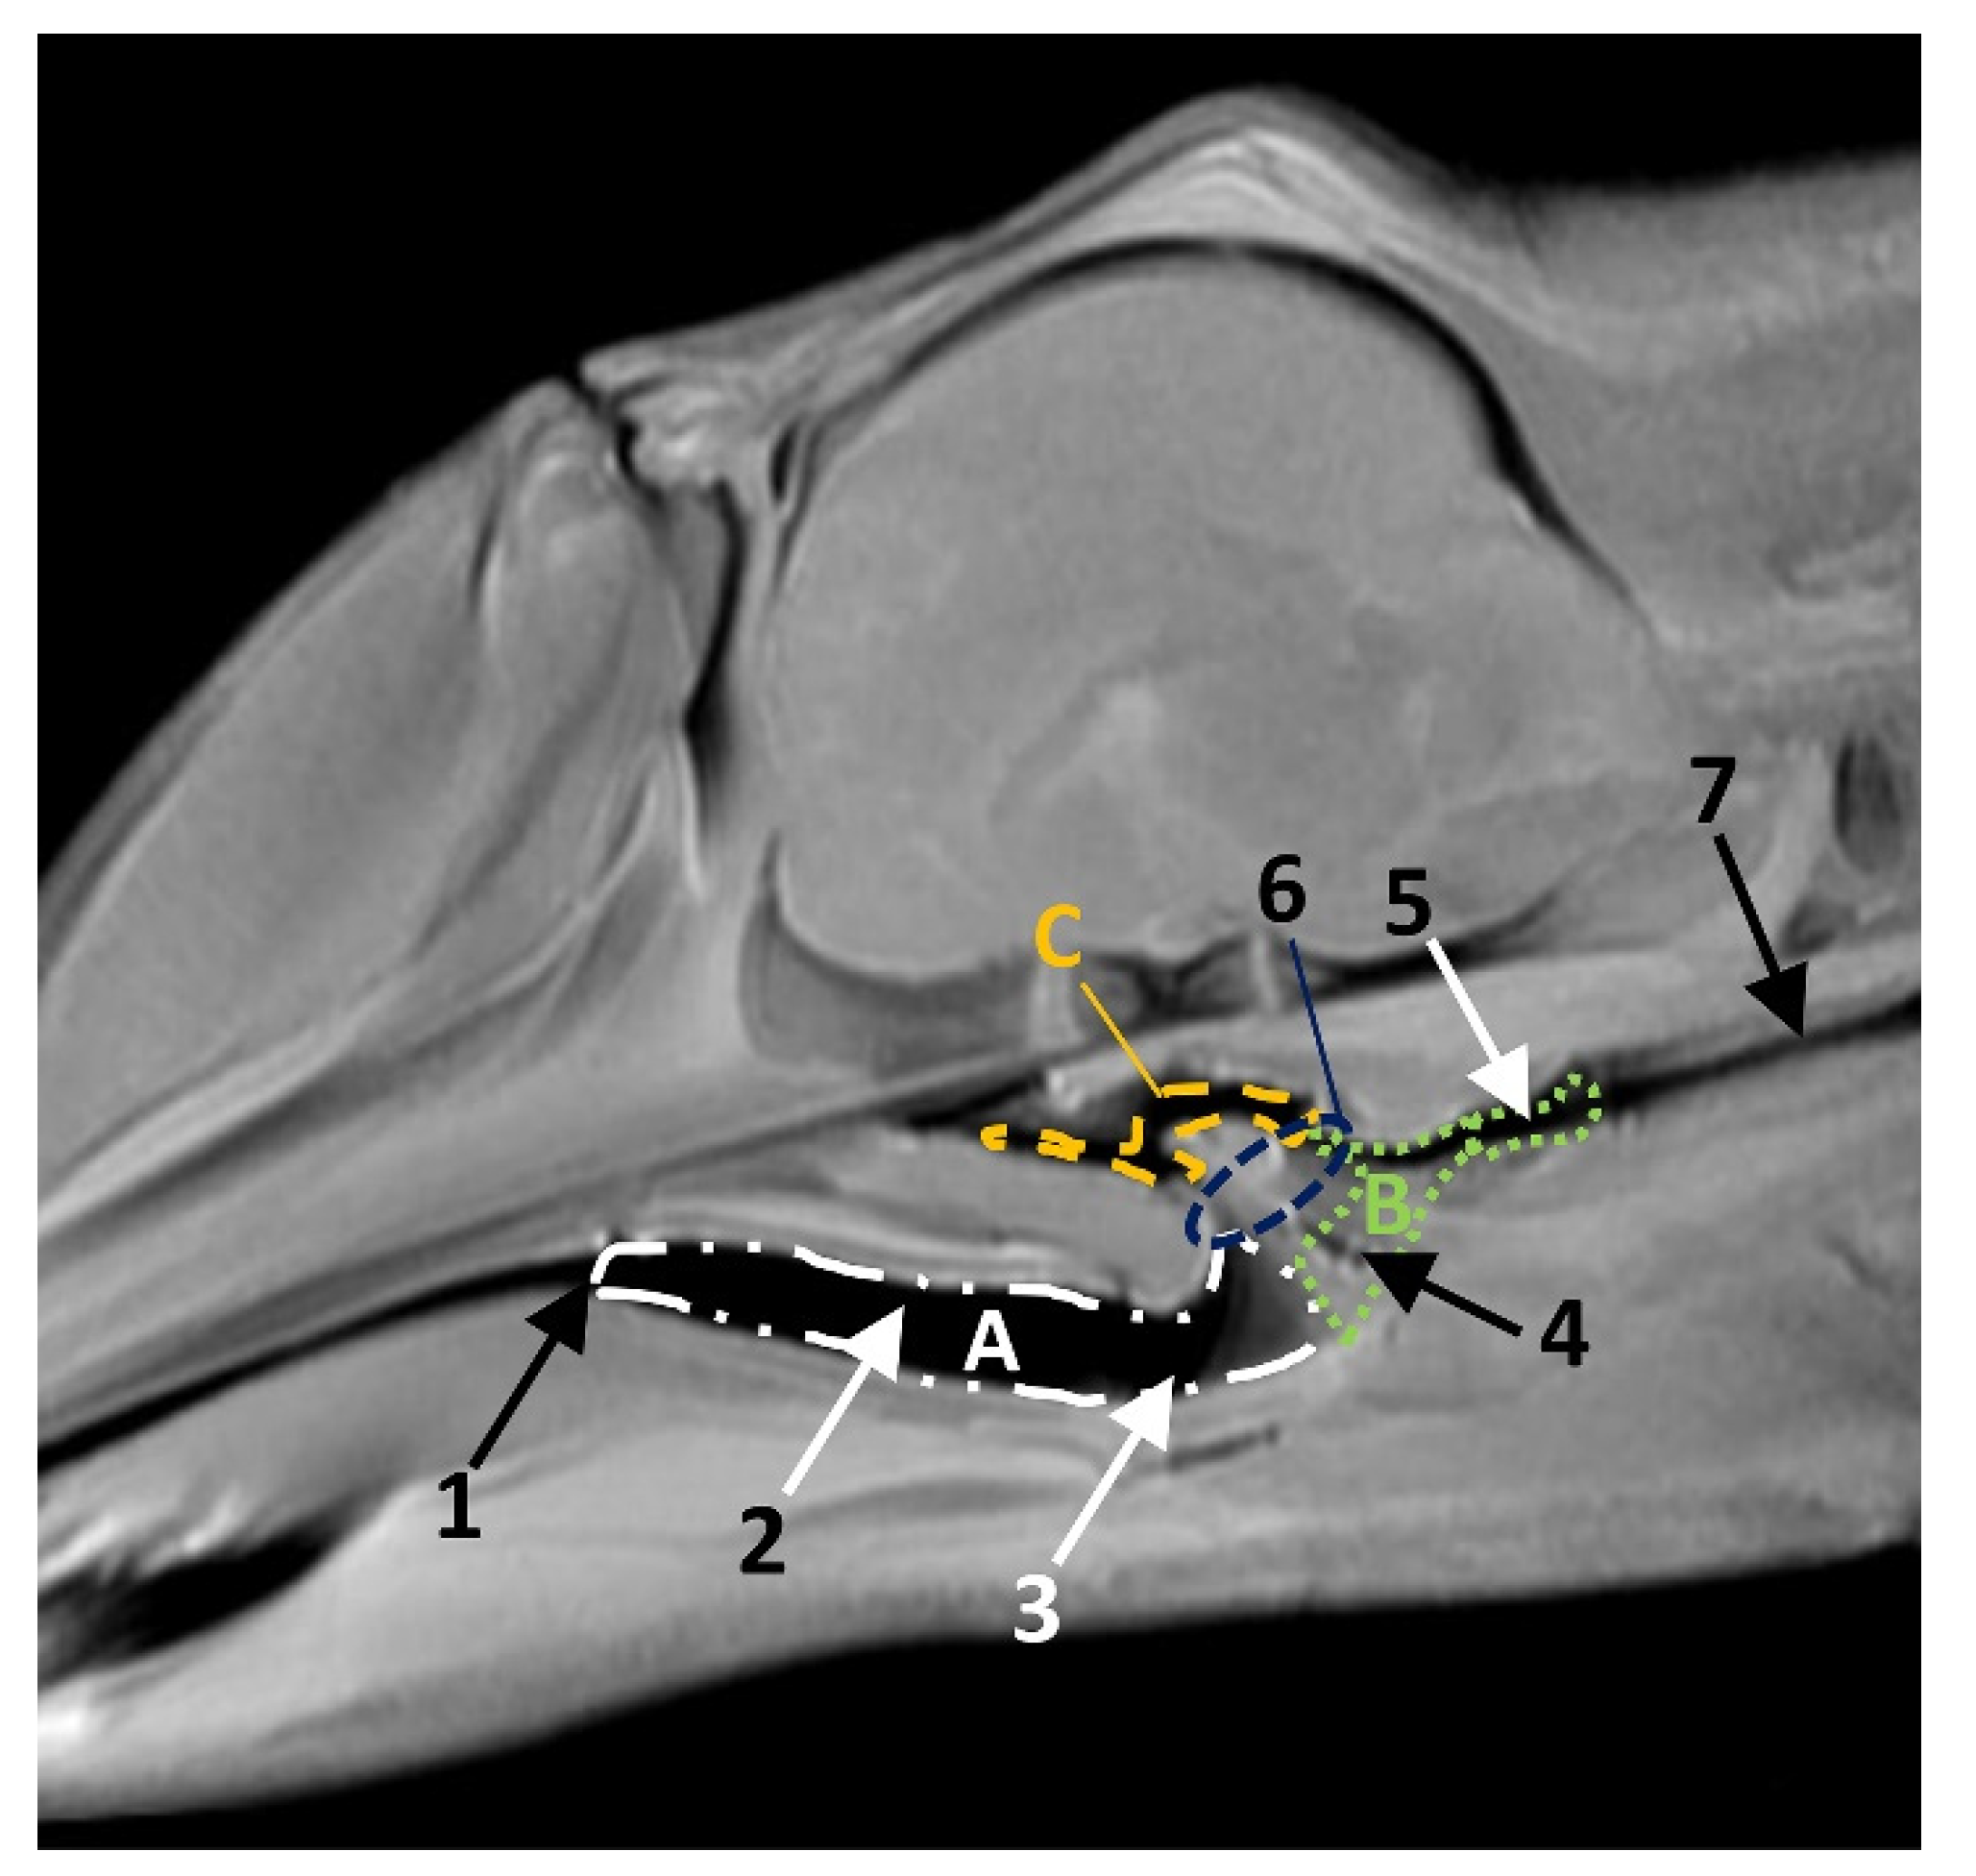

In MRI, we can appreciate, in early fetal stages, a bilateral structure within the laryngopharyngeal cavity, each named as a pharyngeal diverticulum of the auditory tube (PDAT). These are connected through the musculotubaric channel with the middle ear (temporal bone: petrous and tympanic part). In a young Delphinus delphis fetus (dde3), it appears in sagittal sections as a hyper/hypointense area seen caudal and rostrally, respectively (Figure 26A,B), and also in coronal sections (Figure 26C,D).

Figure 26.

Images of the pharyngeal cavity. MR sagittal and coronal images are oriented so that the rostral is to the right. (A) T1 SE sagittal, (B) T2 FrFSE sagittal, (C) T1 SE coronal and (D) T2 FrFSE coronal planes. 4 months, dde3. 1, Inner and middle ear; 2, Pharyngeal diverticulum of the auditory tube.

In older Delphinus delphis fetuses (dde5, dde8, dde11) this double space at both sides of the laryngopharynx is more evident and shows the same intensity, but now we can distinguish the vascular area (hyperintense) and the air-filled area (hypointense) (Figure 27, Figure 28, Figure 29, Figure 30 and Figure 31).

Figure 27.

Images of the pharyngeal cavity. MR coronal and sagittal images are oriented so that the rostral is to the right. (A,B) T2 FrFSE sagittal, (C) T1 SE and (D) T2 FrFSE coronal planes. 5.5 months, dde5. 1, Inner ear; 2, Pharyngeal diverticulum of the auditory tube: moderate hyperintense area (vascular); 3, Pharyngeal diverticulum of the auditory tube: hypointense area (air).

In more advanced fetal development, it is possible to observe air (hypointense) and vascular (moderate hyperintense) areas, and even the auditory tube (slightly hypointense) (Figure 30).

PDAT were clearly seen in sagittal and coronal sections in a Grampus griseus fetus (grgr1). The T2 sequences are clearer than T1 because they differentiate two areas: slightly hypointense (vascular) and hyperintense (air) (Figure 31).

The PDAT is a well delimited area, even in the early stages of fetal development (Figure 2). This area is medially extended to the bony choanae and extends dorsally to the maxillopalatine fossa, medially to the pterygopalatine recess (pterygoid sinus) and rostrally to the petrous and tympanic parts of the temporal bone (cochlea) (Figure 33).

Figure 33.

Common dolphin skull. Dots show the extension and form of the right pharyngeal diverticulum of the auditory tube. Photography Francisco Gil Cano. Courtesy from Ángel Tórtola. Spanish naturalist. Oblique view. dde15. 1, Greater palatine groove; 2, Palatine bone: perpendicular lamina; 3, Palatine bone: horizontal lamina; 4, Vomer bone; 5, Pterygoid bone: medial lamina; 6, Pterygoid bone: lateral lamina; 7, Pterygoid bone: crest; 8, Lacrimal and zygomatic bone; 9, Temporal process of the zygomatic bone; 10, Frontal bone; 11, Presphenoid bone: wings; 12; Basisphenoid bone: wings; 13, Temporal bone: squamous part; 14, Temporal bone: petrous and tympanic parts; 15, Occipital bone: basilar part; 16, PDAT area; 17, Maxilopalatine fossa (pterygopalatine fossa in mammals); 18, Pterygopalatyne recess (pterygoid sinus); 19, Maxillary bone: palatine process.

The two sagittal sections in a juvenile Stenella coeruleoalba (scomu3) were made para-sagittally at the level of the ear. It shows that this area (PDAT) extends rostrally to the inner and middle ear crossing below the basal bones of the cranium to arrive to the pterygopalatine recess (pterygoid sinus) and finish dorsally at the maxillopalatine fossa (Figure 35).

Figure 35.

(A,B) Detailed serial sagittal sections at level of the pharyngeal diverticulum of the auditory tube with an anfractuous mucosa filled with a heterogeneous content. It extends up to the maxillopalatine fossa rostral to the eyeball. scomu3. 1, Middle and inner ear; 2, Pharyngeal diverticulum of the auditory tube; 3, Occipital bone: basilar part; 4, Basisphenoid bone; 5, Presphenoid and ethmoid bones; 6, Pterygoid bone; 7, Palatine bone; 8, Maxilopalatine fossa (pterygopalatine fossa in domestic mammals); 9, Pterygopalatine recess (pterygoid sinus).

In the adult Stenella coeruleoalba (scomu6), the pharyngeal orifice of the auditory tube is canalized by a trocar (Figure 36A) and the PDAT area is located ventrally. The enlarged image shows, after removing the pharyngeal muscles, the trajectory of the auditory tube towards the pharyngeal diverticulum (Figure 36B).

Figure 36.

(A) Sagittal section of head at level of nasal, pharyngeal and oral cavity. (B) Detail of the trajectory of the trocar towards the pharyngeal diverticulum after removing the pharyngeal muscles around the auditory tube. Adult, scomu6. 1, Nasal cavity: vestibule; 2, External nares muscles; 3, Phonic lips; 4, Nasal plug; 5, Nasal plug muscles; 6, Nasal cavity: respiratory part; 7, Nasal cavity: incisive recess; 8, Choanae; 9, Melon; 10, Pharyngeal muscles; 11, Nasal bone; 12, Frontal bone; 13, Ethmoid bone; 14, Presphenoid bone; 15, Basisphenoid bone; 16, Incisive bone; 17, Maxillary bone; 18, Pterygoid bone; 19, Mesethmoid cartilage; 20, Pharyngeal diverticulum of the auditory tube (rostral part is pterygoid sinus); 21, Pterygopalatine recess (pterigoyd sinus); 22, Hypophysis; 23, Connection orifice; 24, Tongue: proper lingual muscle; 25, Hyoglossus muscle; 26, Geniohyoid muscle; 27, Mylohyoid muscle; 28, Digastricus muscle; 29, Musculotubaric channel; 30, Middle ear (petrotympanic bone); 31, Trocar inserted in the pharyngeal orifice of the auditory tube; 32, Trocar (showing duct trajectory).